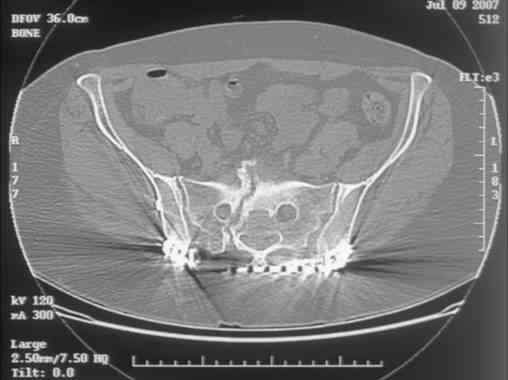

Looking for advice. This is a 48 yo non-smoking female s/p MCC 10 months ago. I do not have the initial injury films. She underwent ORIF as shown on attached file. She is having continued pain in low back/sacral region. Worse with sitting and prolonged walking. Has had pain since surgery. All of her wounds have healed uneventfully. Also has right hip pain laterally. No groin pain. Not aggravated with ROM of the hip. Infection work-up has been negative.

Any thoughts on the broken plate on the pelvic brim and the non-union on the anterior column. Doesn't seem like she's have pain from there.

Maybe remove the disengaged iliosacral screw first to see if she improves?

I can't see the axial CT images well enough to detail the potential sacral issues....can you magnify them?

Here is a magnified view. Sorry about the quality but the CT was scanned into our system.